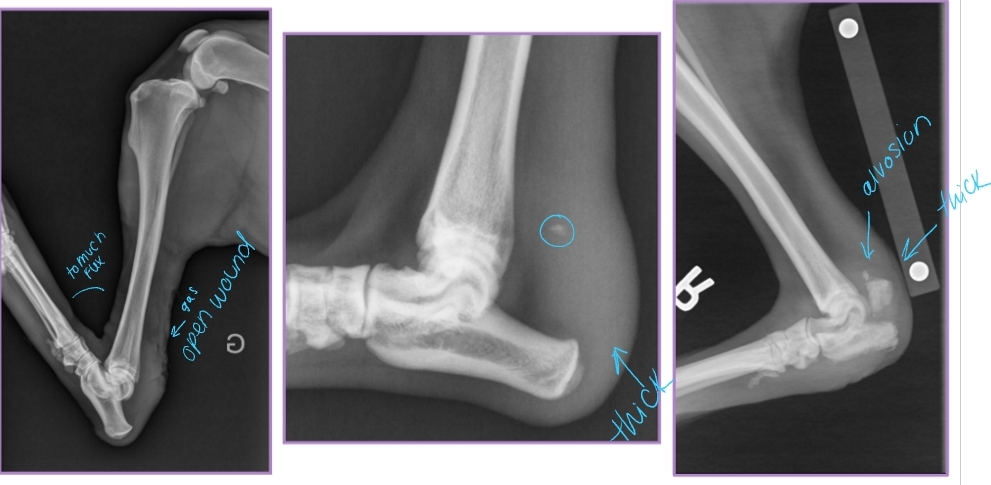

Elbow Luxation

Et: Traumatic most common

Traumatic: Radius and ulna luxate laterally

large medial condyle of humerus prevents medial luxation

Congenital: abnormally shaped radius/ulna/ humerus

Cs: Unable to bear weight, Forelimb abducted and externally rotated (elbow out, paw rotated in)

Dt: limb resists extension, prominent radial head, PAINFUL, Radiographs AP views!

Tx:

Acquired: Closed reduction under GA + brachial plexus block

Flex elbow to 100° and internally rotate

Extend elbow slightly, adduct and inwardly rotate antebrachium while applying medial pressure on radial head

Immobilize 2 weeks w/ spica split

Congenital

If reducible → place transarticular pin while still growing!! remove later on

If non-reducible → arthrodesis when older in standing position